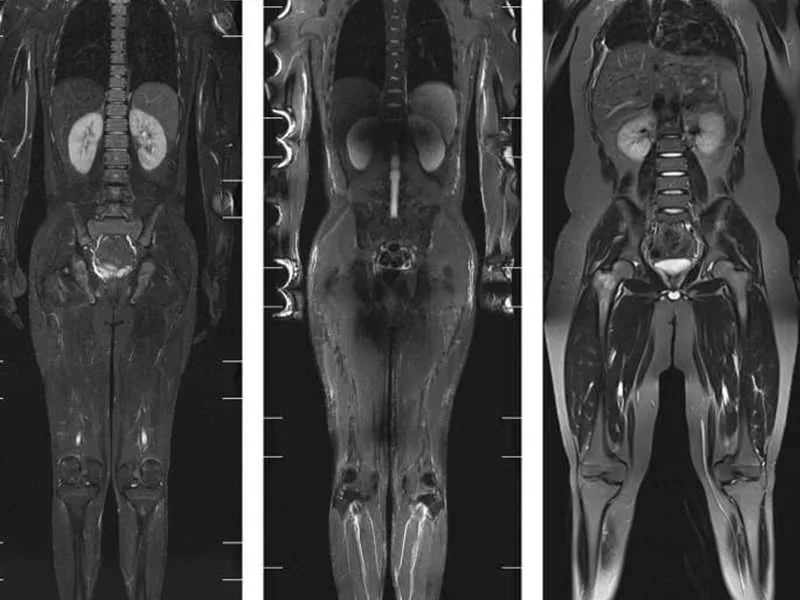

Tüm vücut MR, manyetik rezonans görüntüleme teknolojisi kullanılarak vücudun tamamının ayrıntılı bir şekilde taranmasıdır. Radyasyon içermeyen bu yöntem, manyetik alan ve radyo dalgaları yardımıyla organların ve dokuların yapısını detaylı bir şekilde gösterir. Doktorlar, bu görüntüleri kullanarak hastalıkları teşhis eder ve tedavi planlarını oluşturur.

Tüm vücut MR, özel bir cihazda yatay pozisyonda yatarak gerçekleştirilir. Hasta, cihazın içinde hareketsiz kalır ve manyetik alan ile radyo dalgaları yardımıyla görüntüler elde edilir.